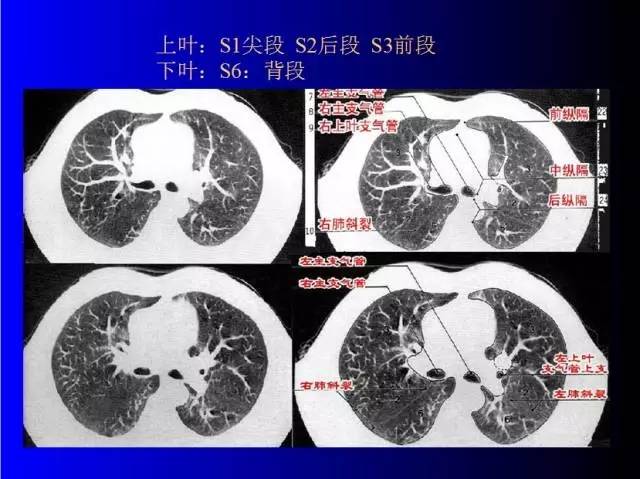

肺部基础X片及CT片解读